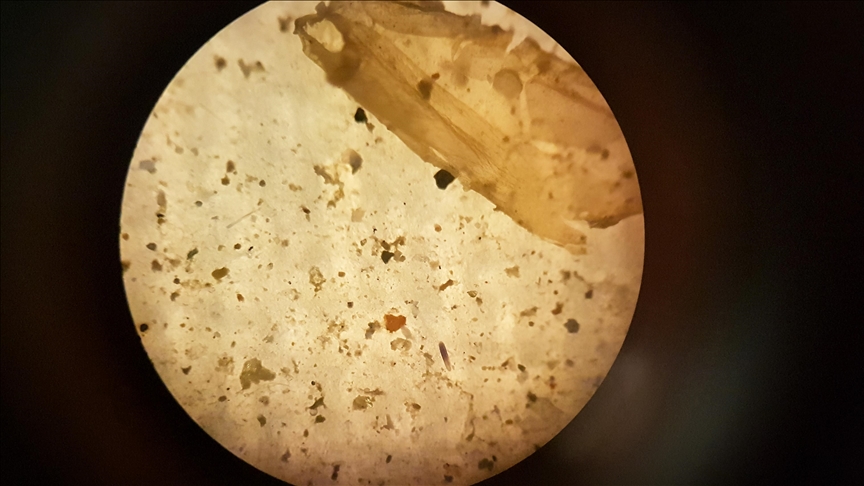

Grimca mikroplastike të zbuluara në 90 për qind të mostrave të indeve kancerogjene dhe 70 për qind të mostrave jo kancerogjene, sipas studiuesve në NYU Langone Health